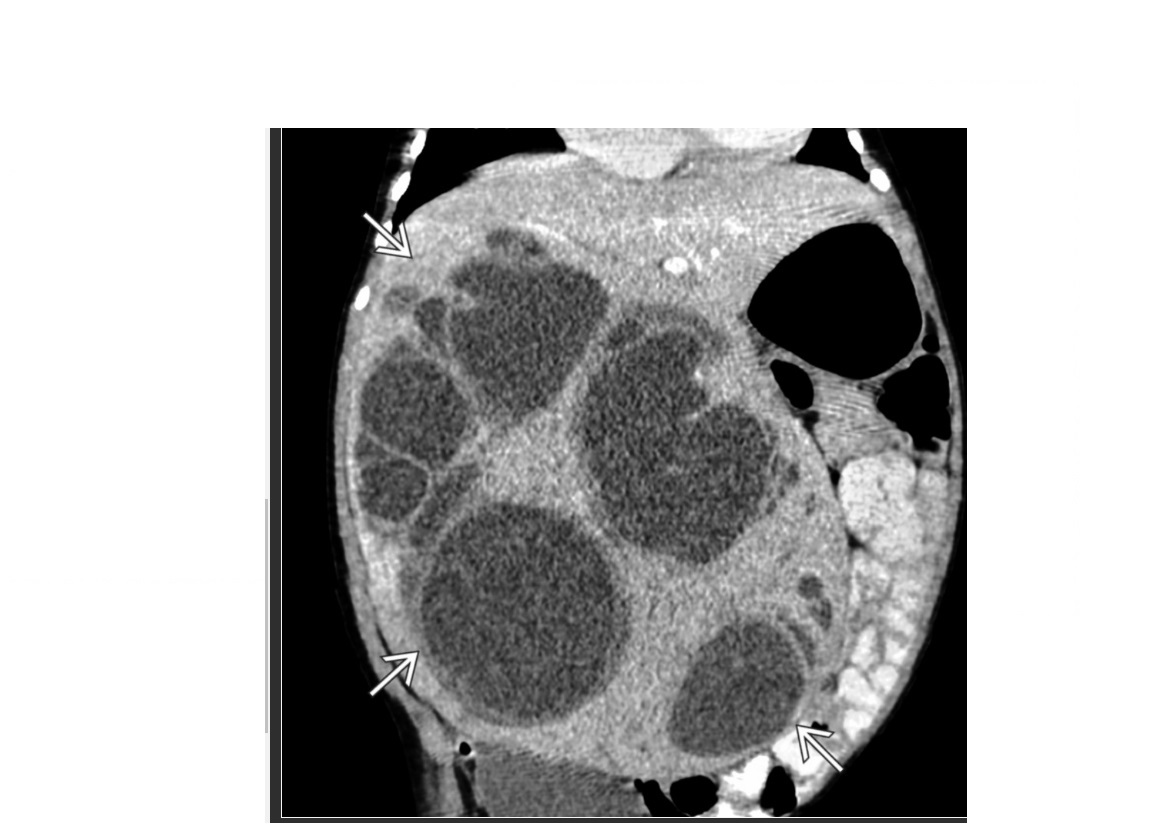

Key features of neuroblastoma?

Peak age is 2 Most adrenal in location, 1/3 retroperitoneum and 1/5 posterior mediastinum. Secrete catecholamines = hypertension ir VIP = watery diarrhoea **ENCASES the IVC ** Crosses midline **Ca2+ ** 'Dropping lily sign' on urography - kidney displaced Downard's **Staging is performed with an 123I-MIBG scan ** Stage IVs (disease involving the skin, bone marrow and liver) which has the best prognosis.

65

Key features of Wilms (nephroblastoma) tumour?

peak age 3-4 **Displaces +/- invades the IVC ** less commonly crosses the midline or Ca2+ 'Claw sign' - Rim of normal renal tissue extending around the mass. 10% tumour - Ca2+ ( curvillnear), vascular invasion, bilateral, lung mets